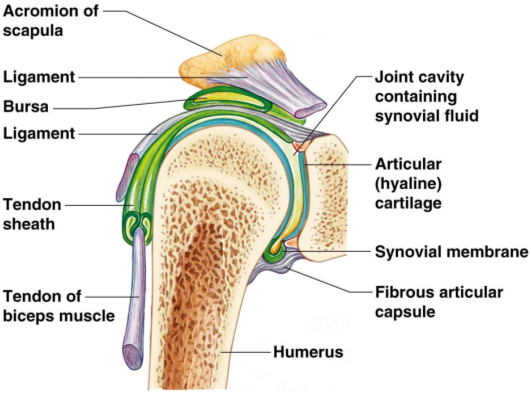

Glenohumeral ligament: анатомия и функции плечевого сустава